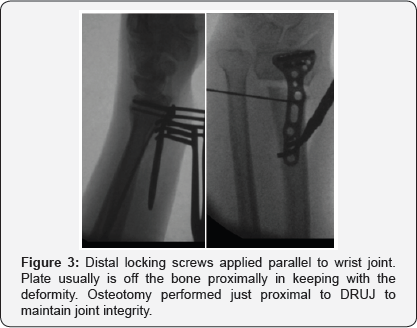

A volar approach to the distal radius extending proximally from the wrist crease along the flexor carpi radialis tendon using a 5-7cms incision, the radial artery identified and protected radially with pronator quadrates elevated along its radial and distal borders and the brachioradialis partially released from its insertion, the volar locking plate of the acumed set was used in all cases (standard size), where the distal end of the plate was aligned with the wrist joint, with the aid of k wires passing through the joint as well as under fluoroscopic image control to align the plate with the required volar tilt and radial inclination, once achieved the distal locking screws were applied. This was followed by the osteotmy being performed as close as possible to the level of deformity, and parallel to the wrist joint, once performed, the radius is pulled out to length with the aid of a laminar spreader applied at the osteotmy site and a cortical screw placed proximally to give the counter pressure required to regain the required radial height and ulna variance. Once corrected the plate was held in place and the first proximal screw was drilled through the oval hole to allow for further fine tuning followed by application of proximal locking screws through the rest of the plate holes (pictures), this was followed by cancellous bone graft harvesting from the same side iliac crest and the amount taken depending on the gap required to be filled at the osteotomy site, cortical bone graft was not added in any of the procedures, the pronator quadratus was brought back to its original position and the subcutaneous layer and skin were sutured using absorbable sutures. All patients had a below elbow well padded splint and discharged the same or the following day to surgery (Figures 1-4).